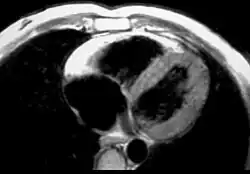

- Dysfunkcje globalne lub regionalne i odmienności strukturalne (Rozpoznane w echokardiografii, angiografii, MRI lub scyntygrafii serca)

- Kryteria duże

- Znaczne poszerzenie i redukcja frakcji wyrzutowej prawej komory i brak lub niewielkie upośledzenie czynności skurczowej lewej komory

- Tętniaki prawej komory (obszary akinezy lub dyskinezy z diastolicznymi wybrzuszeniami). Znaczne odcinkowe poszerzenie prawej komory

- Łagodna rozstrzeń prawej komory lub łagodne zmniejszenie frakcji wyrzutowej i prawidłowa lewa komora

- Łagodne odcinkowe poszerzenie prawej komory

- Miejscowa hipokineza prawej komory